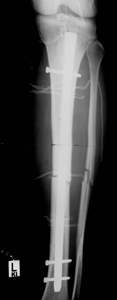

der Verfahrenswechsel zum Verriegelungsnagel möglich. Die primäre

Nagelung ist auch mit einem sogenannten ungebohrten Nagel zu riskant.

Das Infektionsrisiko beim Verfahrenswechsel ist gering, wenn dieser

innerhalb von 2-3 Wochen erfolgt.

Dynamischer Fixateur und Verriegelungsnagel angeboten werden. Beim

Verfahrenswechsel bevorzugen wir den Titannagel T2, da uns bei diesem

Nagel das Infektionsrisiko geringer erscheint. Die Ausheilungszeit

ist bei beiden Verfahren zwar gleichwertig, aber der T2 Nagel wird

von den Patieten besser akzeptiert.